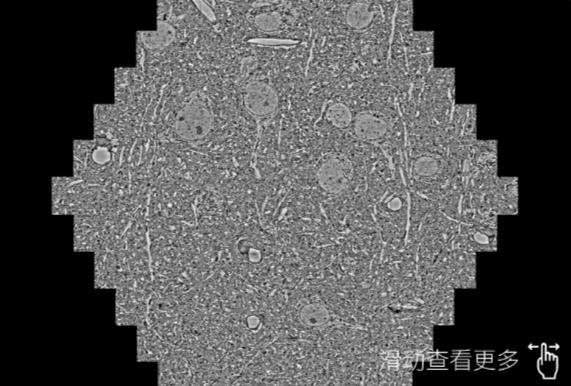

鼠脑切片。左图使用三明蔡司三明扫描电镜MultiSEM706对165μmx143pm面积区域成像,耗时仅需1.5秒。右图为鼠脑切片中30μm区域放大效果。样品由芝加哥大学B.Kasthuri提供。

使用蔡司高速三明扫描电镜MultiSEM对1mm²人脑皮层组织进行高分辨成像,并对其中的各种细胞结构进行三维重构分析。左图展示了2x3mm²组织平面中锥体神经元的三维重构效果。右图显示了局部体积神经元三维重构。图像由哈佛大学chtman实验室提供,渲染图由D. Berger 制作。